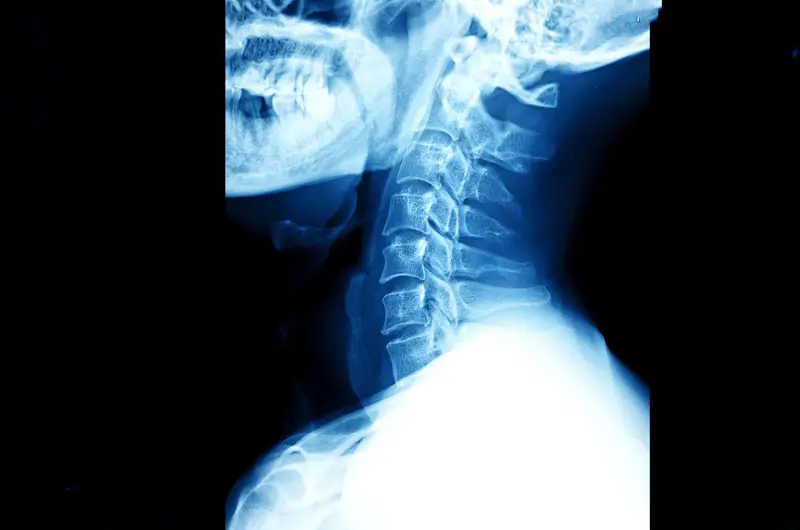

Cervical disc disorders and displacements are the other common conditions treated at orthopedic practices apart from fractures and injuries. With the implementation of ICD-10, practices require more specific data to report cervical disorders and displacements and ensure accurate orthopedics medical coding to receive timely reimbursement. There are specific codes for disorders depending upon the various regions of the cervical spine (high cervical C2-3 and C3-4; mid-cervical C4-5, C5-6, and C6-7; cervicothoracic C7-T1). If the region is unclear, you should use unspecific region codes. The new coding system requires the indication of myelopathy and radiculopathy as well. Let’s consider the different types of cervical disc disorders.

This condition occurs when the intervertebral discs at the cervical region degenerate or break down due to aging (repeated daily stress). This is the common cause for stiff neck and requires physical examination and even imaging studies for diagnosis. There was only one code in ICD-9 to report this condition.

This condition occurs when the inner core of a disc in the neck herniates, or leaks out of the disc. The pain radiates along the nerve pathway to the arm causing neck pain, arm pain along with numbing and tingling. Special imaging diagnostic studies may be required to better diagnose this condition. The diagnostic codes are as follows.

This refers to a cervical disorder that results in myelopathy (spinal cord gets compressed and causes incoordination in the hands, a heavy feeling in the legs, or numbness and tingling in the legs). Imaging diagnostic studies are required to diagnose cervical disc disorder with myelopathy. The codes are: